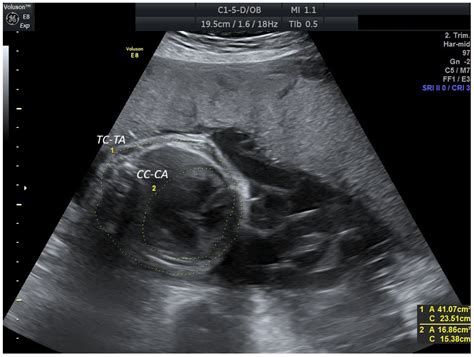

The identification of a Persistent Right Umbilical Vein is primarily achieved through high-resolution fetal ultrasonography. During the mid-trimester scan (typically between 18 and 22 weeks), sonographers examine the fetal abdomen to ensure that the umbilical vein is entering the liver correctly. When a PRUV is present, the sonographer will observe the following characteristic signs:

• The umbilical vein courses to the right side of the gallbladder, rather than the left.

• The vessel takes a slightly different anatomical path toward the portal system.

• The color Doppler ultrasound shows a change in the direction of the vascular flow compared to the expected norm.

Because these findings can be subtle, ultrasound technicians and maternal-fetal medicine specialists are trained to look for these specific markers when the abdominal anatomy does not appear completely symmetrical. Once identified, the radiologist or obstetrician will conduct a detailed survey of the entire fetus to rule out any associated structural abnormalities.